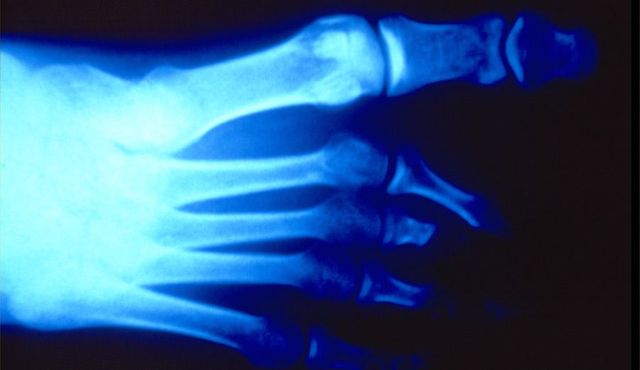

Dokumente des Grauens: Röntgenaufnahmen von Folteropfern

Hermann Vogel: Fotos von Folteropfern sind oft so brutal und direkt, dass der Betrachter reflexartig wegschaut. Anonyme Röntgenbilder sind besser auszuhalten. Zunächst erkennt der Betrachter nur, dass ein Finger fehlt oder ein Knochen zerbrochen ist. Das weckt sein Interesse und er will erfahren, was dem Menschen passiert ist. Die Bilder führen also dazu, dass sich die Menschen mit dem Thema Folter beschäftigen – auf erträgliche Weise. Und genau das ist mein Ziel.

Sie entlarven von außen nicht erkennbare Verletzungen, somit auch Spuren von Folter. Eine gerichtsmedizinische Untersuchung macht Frakturen, eingeführte Fremdkörper, Nadeln sichtbar. Die Aufnahmen ermöglichen eine Plausibilitätsprüfung. Stimmen die Schilderungen des Opfers mit dem Verletzungsmuster überein? Stimmt das Alter der Verletzung überein mit dem Zeitraum, den die Person für die erfahrene Folter angibt? Entspricht die Foltermethode dem, was für die angegebene Region und die verantwortliche Organisation, Militär oder Miliz, bekannt ist?